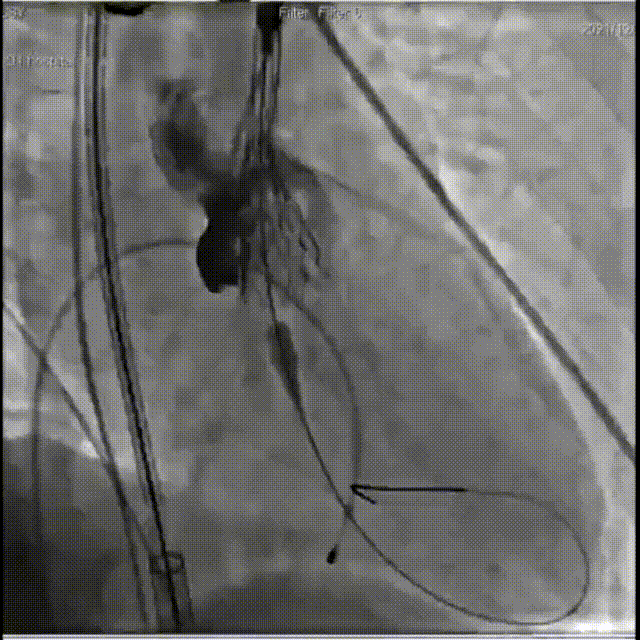

患者全麻状态下,穿刺颈静脉,植入临时起搏电级,电级置入右室心尖,穿刺左侧股动脉,建立辅入路。穿刺右侧股动脉作为主入路,跨瓣成功后,予以22mm球囊预扩张观察,冠脉血流正常,根据术前预案,植入TAV27型号瓣膜,选择高位释放。瓣膜植入后,超声评估瓣膜位置良好,形态完整,轻微瓣周漏。术中及术后均无相关并发症,手术取得了圆满成功!

瓣膜定位

瓣膜释放

释放后造影, 瓣膜形态良好, 同时无瓣周漏